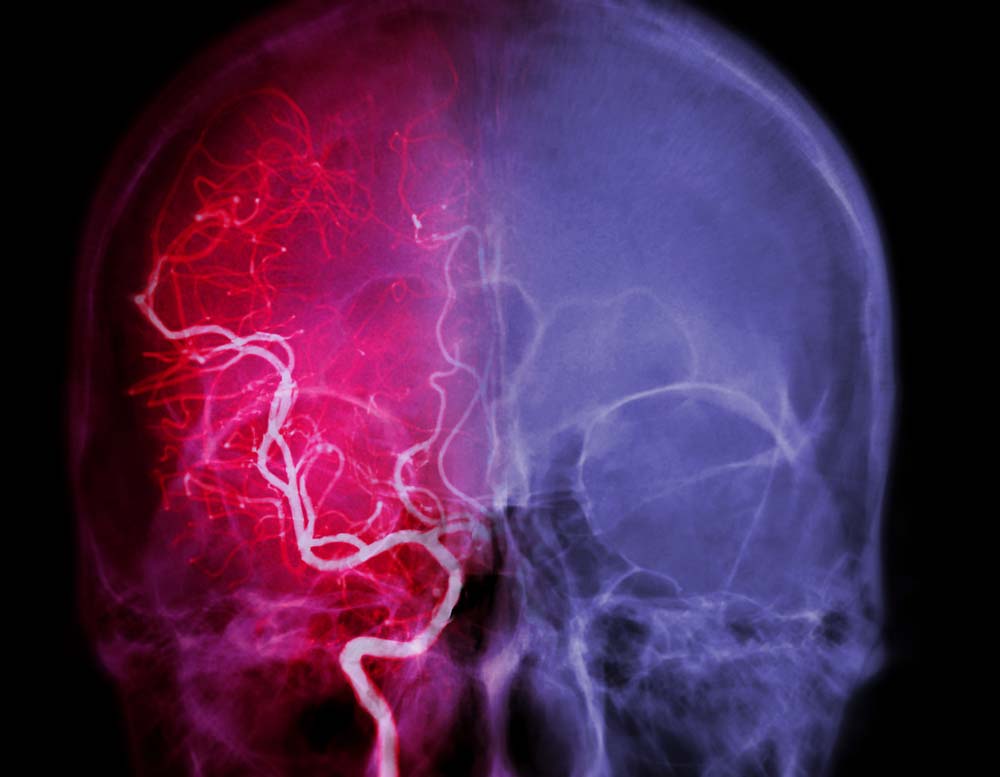

뇌의 대혈관이 막히거나 손상되면 뇌졸중, 뇌출혈 등처럼 증상이 명확히 나타난다. 하지만 뇌소혈관질환은 초기 단계 증상이 매우 미미하고 모호해 알아차리기 어렵다. 이대로 방치하면 뇌는 서서히 기능을 잃어간다. 주로 ▲손 떨림 ▲걸음걸이 느려짐 ▲언어 장애 ▲한쪽 입가나 손발 마비 등의 증상이 미세하게 보인다. 이땐 바로 병원을 찾아야 한다.